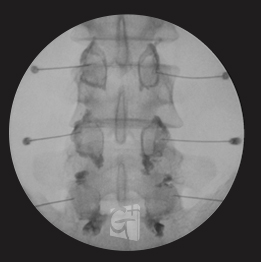

선택적 신경치료

디스크로 인해 눌리고 있는 신경을 선택적으로 치료하는 시술입니다.

경추 선택적 신경치료

경추 6번에서 시행된 선택적 신경치료 약물이 신경근과 추간공 안쪽으로 잘 퍼지는 모습

요추 선택적 신경치료

요추 5번에서 시행된 선택적 신경치료 약물이 신경근과 추가공 안쪽으로 잘 퍼지는 모습